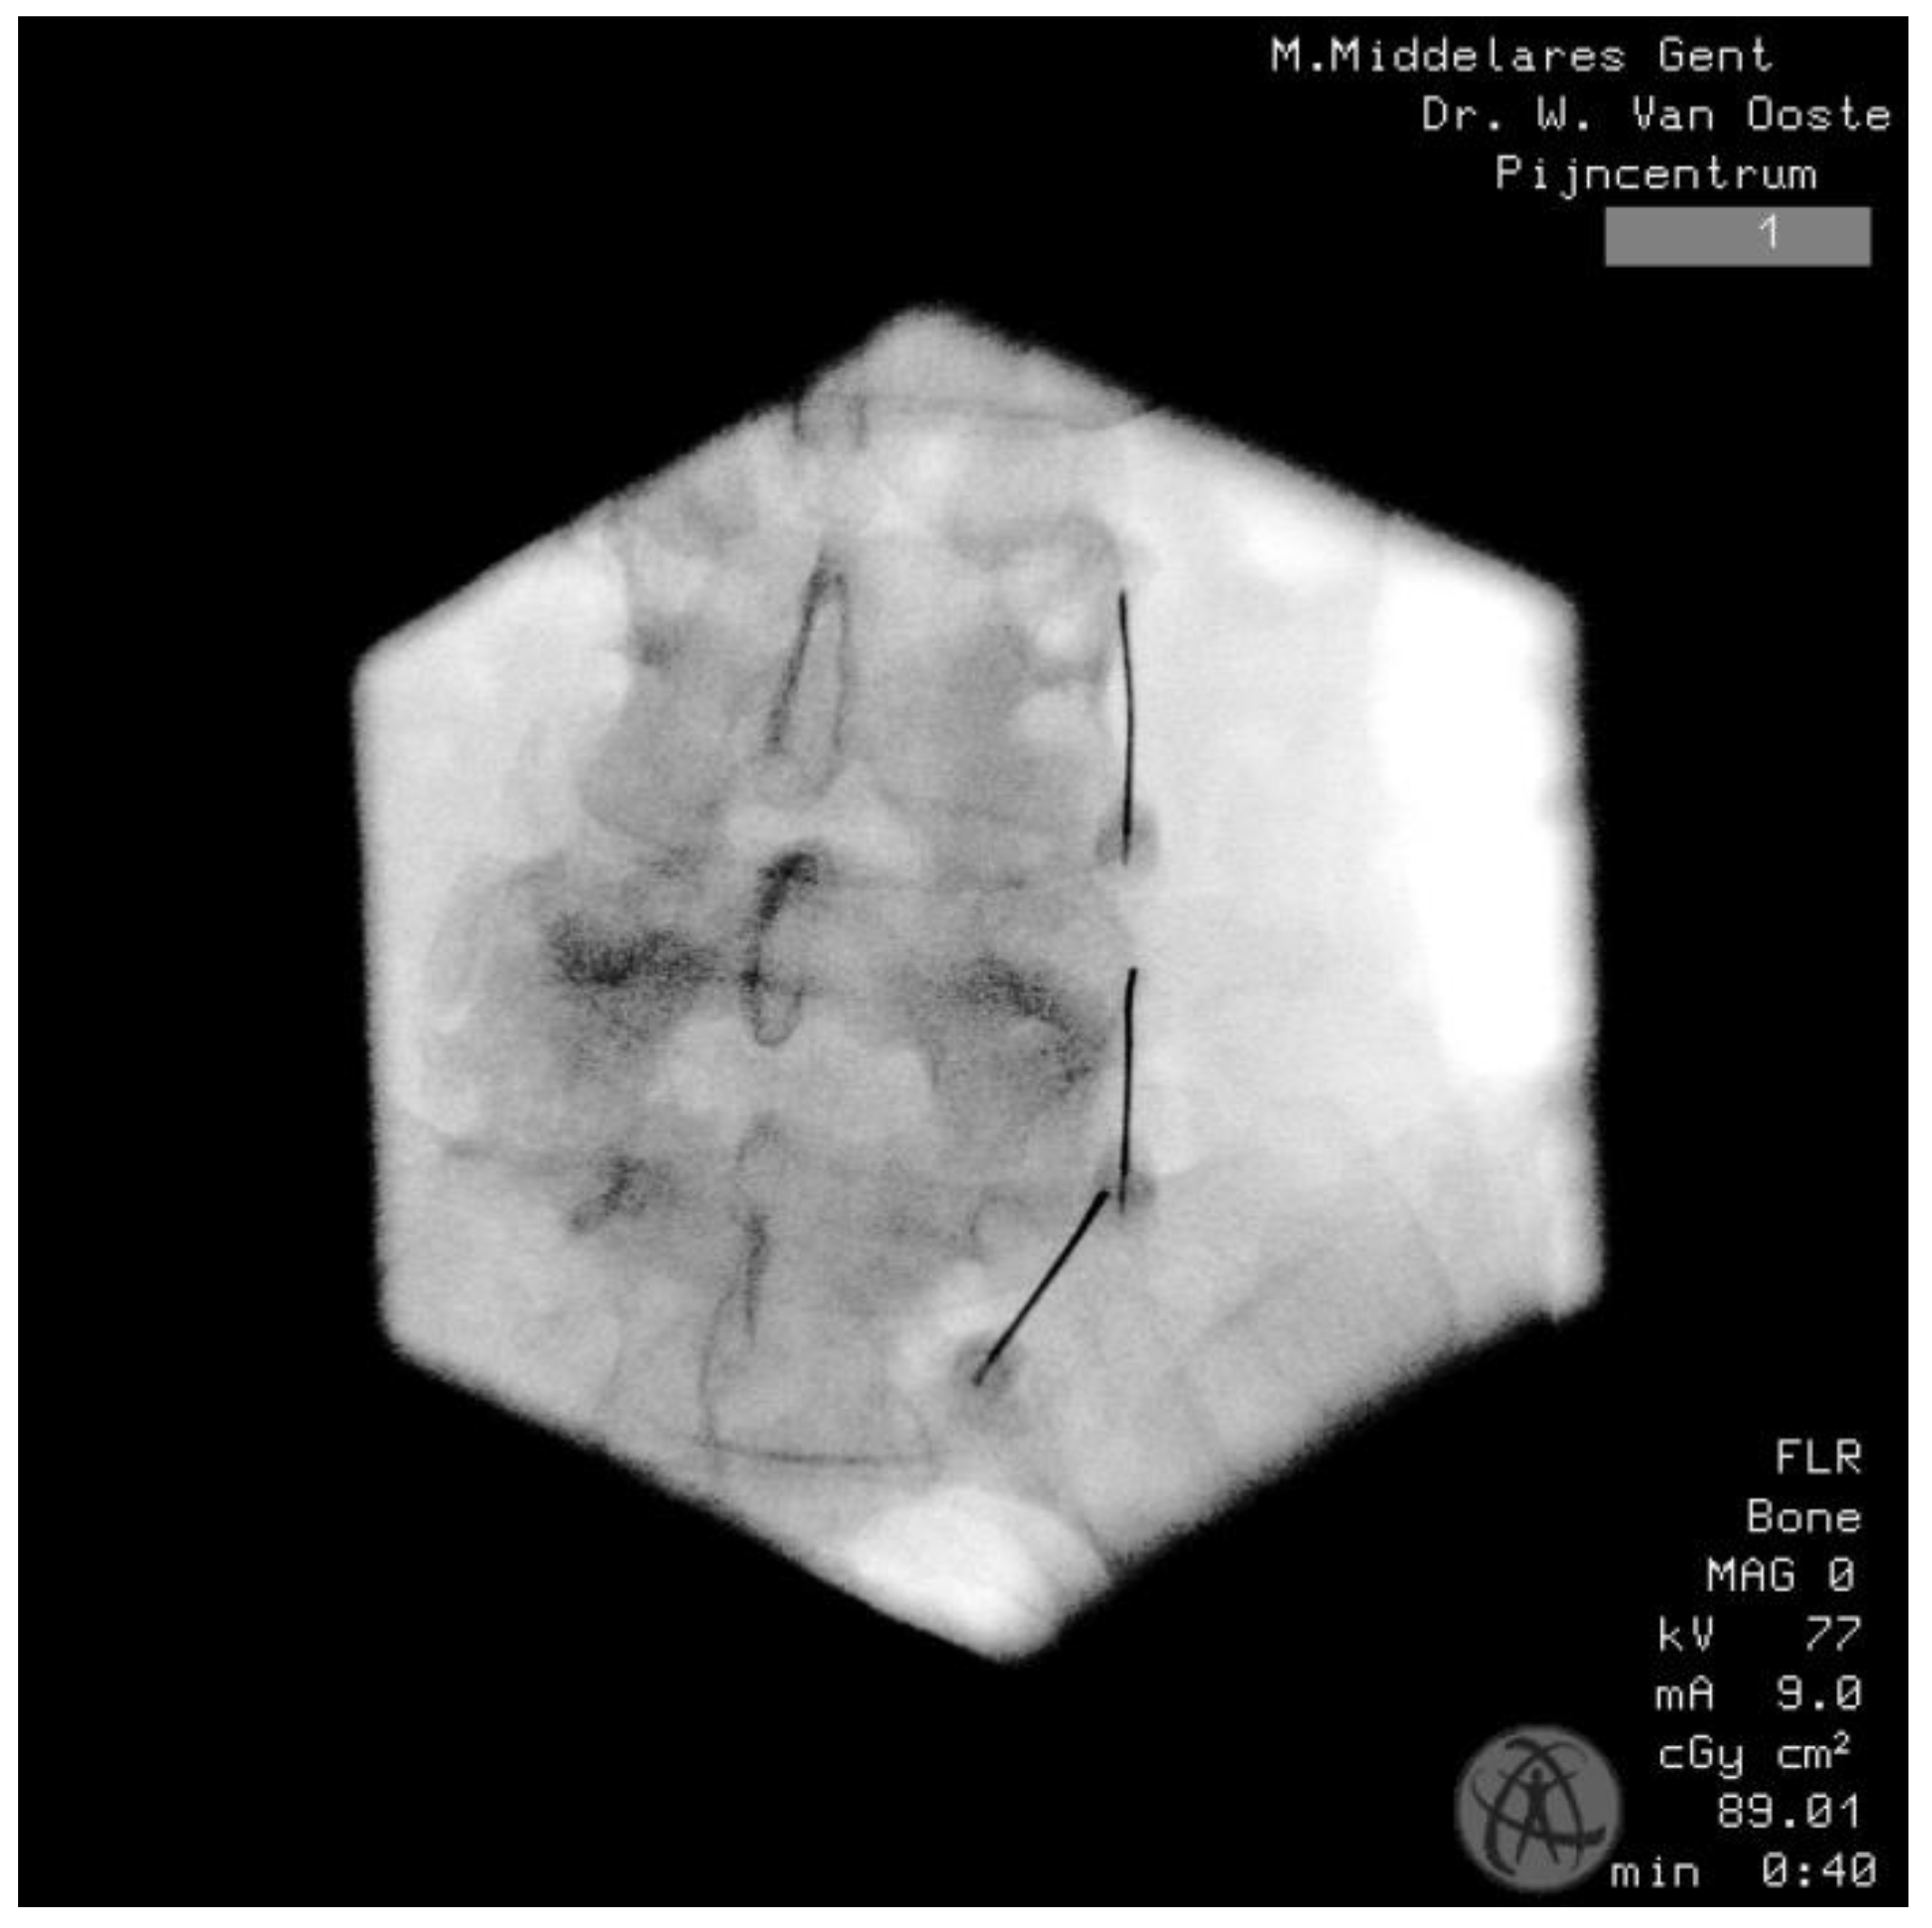

5.6. Medial Branch Blocks

6.4.1. Technique

6.4.2. Orientation

6.4.3. Needle Characteristics and RF Settings

6.4.4. Complications